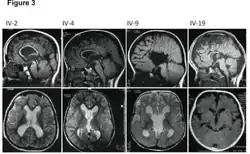

| MRI images showing megalencephaly in four family members who all have unusually large skulls (the family is affected by an autosomal recessive syndrome caused by a KIF7 mutation that induces multiple epiphyseal dysplasia)[1] | |

A mutation in the PI3K-AKT pathway is believed to be the primary cause of brain proliferation and ultimately the root cause of megalencephaly. This mutation has produced a classification of brain overdevelopment that consists of two syndromes including megalencephaly-capillary malformation (MCAP) and megalencephaly-polydactyly-polymicrogyria-hydrocephalus (MPPH).[4] Megalencephaly is usually diagnosed at birth and is confirmed with an MRI.

A neurological exam will then be performed using the technology of an MRI machine in order to confirm the diagnosis of megalencephaly. These imaging tests give detailed information regarding brain size, volume asymmetry and other irregular developments linked with MCAP, MPPH and hemimegalencephaly.[2][21]